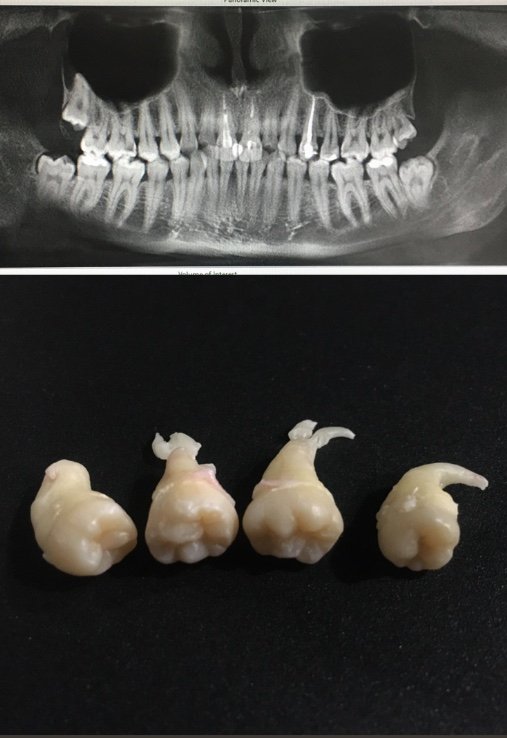

В нашій клініці можна видалити чотири зуби мудрості за одну годину. Але дуже часто ми чуємо від пацієнтів історії про видалення одного зуба протягом години, двох і навіть чотирьох.

— Як правило, ми видаляємо або два, або чотири зуби одночасно. Однак все залежить від побажань пацієнта, тож ми розповідаємо про плюси та мінуси цих варіантів.